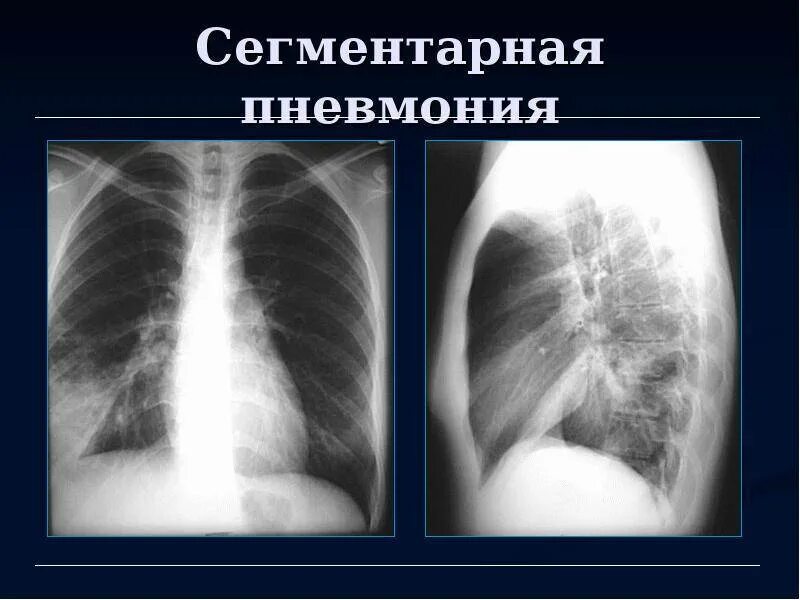

Сегментарная пневмония у взрослых лечение